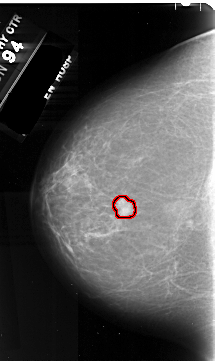

FILE: A_1055_1.LEFT_CC.OVERLAY

TOTAL_ABNORMALITIES 1

ABNORMALITY 1

LESION_TYPE MASS SHAPE IRREGULAR MARGINS SPICULATED

ASSESSMENT 5

SUBTLETY 5

PATHOLOGY MALIGNANT

TOTAL_OUTLINES 1

BOUNDARY